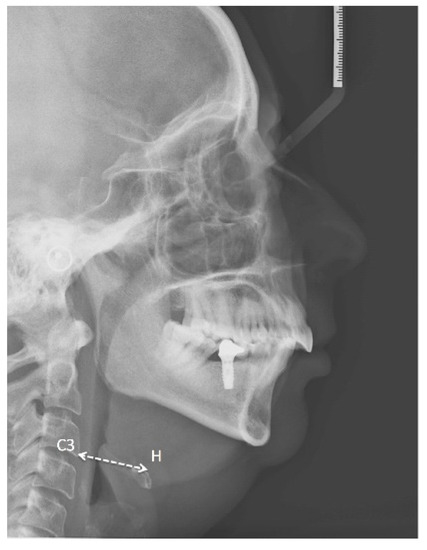

| 11. MPH | HYOID MP PERP Perpendicular to the mandibular plane (PMD) passing through the H point. Distance of the hyoid bone from the lower jaw. |

| 12. HRGn | Hyoid to C3-Retrognathion Line joining point H with point (Retrognation) RGn. Anatomically, this corresponds to the floor of the mouth. |

| 13. C3H | H-C3 Line joining point H with point C3. |

| 14. TGL | Tongue Length (mm). Length of the tongue. |

| 15. TGH | Dorsum of tongue. Maximum height of the dorsum of the tongue. |

| 16. PNSP | PNS to P (see Figure 1). Length of the soft palate. |

| 17. MPT | Maximum soft palate thickness. |

| 18. SPAS | Superior airway space. Measurement (mm) of the airway between the soft palate and the posterior pharyngeal wall along a line parallel to the Go-B plane, passing through the most posterior and superior point of the soft palate. |

| 19. MAS | Middle airway space. Measurement (mm) of the airway between the anterior wall and the posterior pharyngeal wall along a line parallel to the Go-B plane, passing through point P. |

| 20. IAS | Inferior airway space. Measurement (mm) of the airway located between the anterior wall and the posterior pharyngeal wall along the Go-B line. |

| 21. VAL | (PNS-Eb) Oropharyngeal length. |